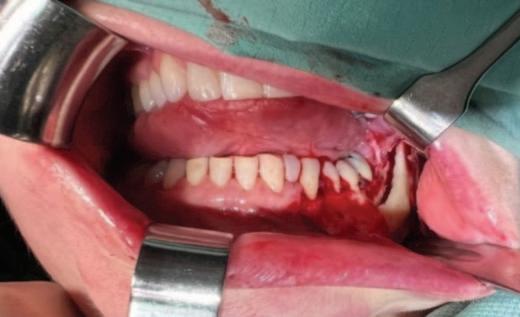

n During the surgery, the upper, inner edge of the window within the guide provides the surgeon with the exact site of the proposed definitive gingival margin location and in doing so, indicates the precise location of the initial internal bevel incision (Figures 4A-4C ).5

n The incisions are usually made with a 15C or SM67 surgical blade (SwannMorton, Sheffield, England). After removal of the excess tissue and revealing of the new crown length, a full-thickness mucoperiosteal flap is raised for direct visualisation of the surrounding bone and the CEJ anatomy. The area for supra-crestal tissue attachment is recreated by osteotomy followed by osteoplasty, using a variety of round end cutting burs and/or Piezo tips. The operator must tailor the distance between the new alveolar osseous crest and the free gingival margin to create a stable

biological width, with average appropriate distances being approximately 2-3mm.6,7 The flap is then repositioned and sutured using internal vertical mattress sutures (Figures 4D-4F ).8